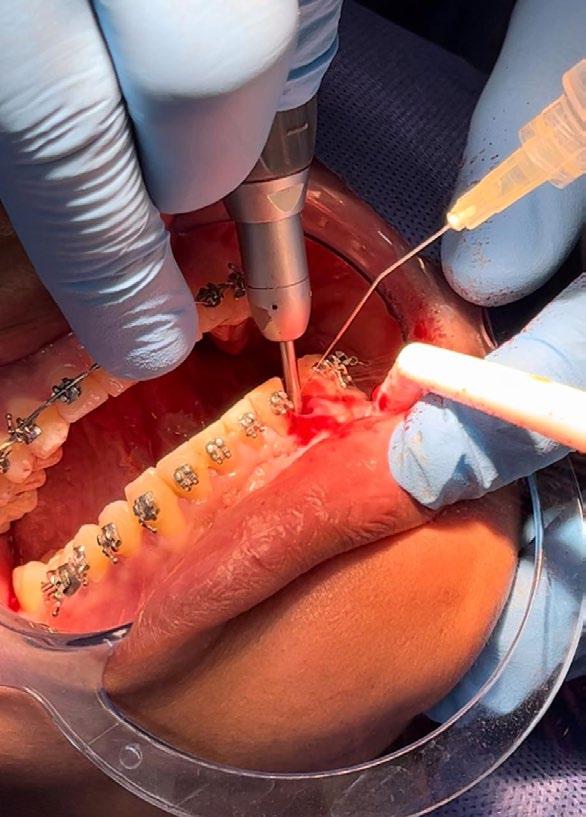

Previa asepsia y antisepsia, más colocación de campos en forma habitual, mediante infiltración troncular y de forma local, se realiza incisión

marginal con descarga lineal para levantar un colgajo seminewman (Figura 3). Se realiza ostectomía y osteotomía para liberar el órgano dentario retenido y facilitar su extracción (Figura 4). Una vez fuera de la cavidad bucal, se realiza tratamiento de conductos y obturación. De forma simultánea, se lleva a cabo la extracción atraumática del órgano dentario 73 (Figura 5) y la preparación alveolar del lecho receptor para recibir el órgano dentario a trasplantar bajo parámetros quirúrgicos (Figura 6).

Figura 5. Primera fase quirúrgica de implantes dentales y segunda fase quirúrgica de colocación de tornillos de cicatrización en la zona de los O.D. 16, 15, 24, 26, 36, 32, 42, 46 y 47.

En la primera fase quirúrgica se colocaron los implantes dentales en las zonas de las piezas 16, 15, 24, 26, 36, 32, 42, 46 y 47. A los 6 meses se evaluó la osteointegración hueso-implante, y